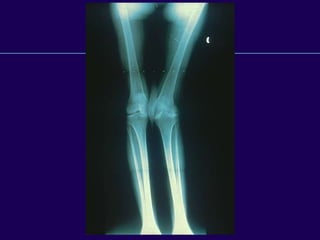

Normal Knee Anatomy

 Position in single leg stance

 Mechanical axis valgus 3º

 Femoral shaft axis valgus 6º

 Proximal tibia varus 3º